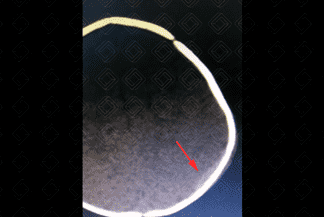

Texto alternativo para a imagem Créditos: Dra. Elazir Mota - Rio de Janeiro/RJ

Descrição da imagem: Tomografia computadorizada do crânio sem contraste. Pequeno foco em crescente, hiperatenuante, na região parietal esquerda (seta vermelha), compatível com hematoma subdural agudo.

• Tomografia computadorizada do crânio (hematoma subdural agudo): Coleção extra-axial em crescente, hiperatenuante e que se estende difusamente pelo hemisfério acometido e, na maioria dos casos, unilateral; há deslocamento das veias corticais e buscar por fraturas;